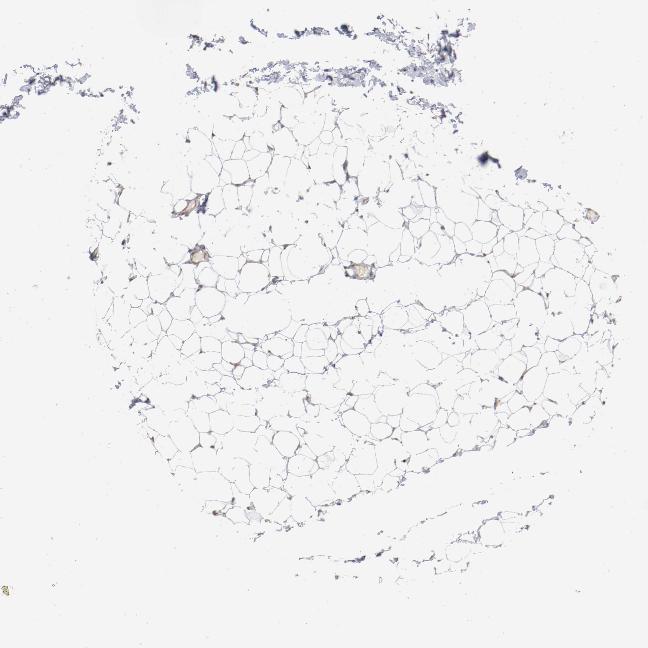

SOFT TISSUE 1 - Antibody stainingi

Antibody staining in the annotated cell types in the current human tissue is reported as not detected, low, medium, or high, based on conventional immunohistochemistry profiling in selected tissues. This score is based on the combination of the staining intensity and fraction of stained cells.

Each image is clickable and will lead to virtual microscopy that enables deeper exploration of all samples and also displays staining intensity scores, fraction scores and subcellular localization as well as patient and tissue information for each sample.

Antibody HPA003578

Fibroblasts Not detected

SOFT TISSUE 2 - Antibody stainingi

Peripheral nerve Not detected